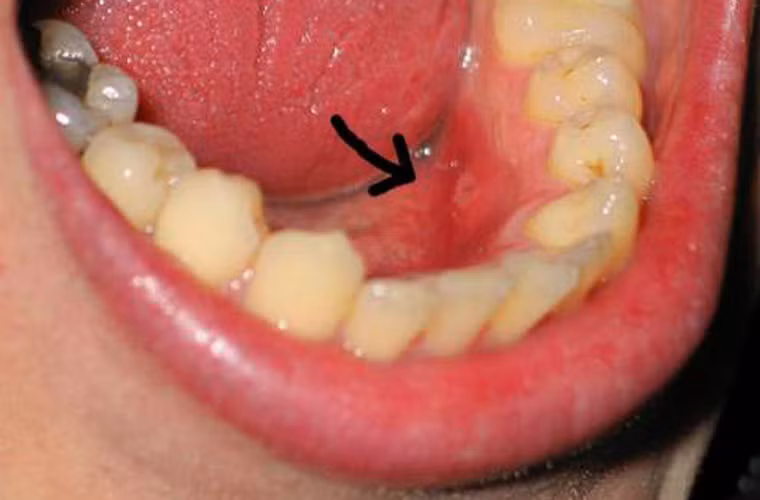

Cụ thể, những người vệ sinh răng miệng kém, có các biểu hiện như nướu răng, hỏng răng sẽ dễ dàng nhiễm virus gây u nhú HPV hơn cả.

Nghiên cứu này không chỉ rõ vì sao vệ sinh răng miệng kém lại làm tăng nguy cơ nhiễm HPV. Tuy nhiên, các nhà khoa học nhấn mạnh virus HPV thường ẩn náu ở những vết thương nhỏ trong miệng hoặc cổ họng. Đặc biệt chỗ bị viêm loét, viêm nướu sẽ giúp HPV nhanh chóng di chuyển vào máu.